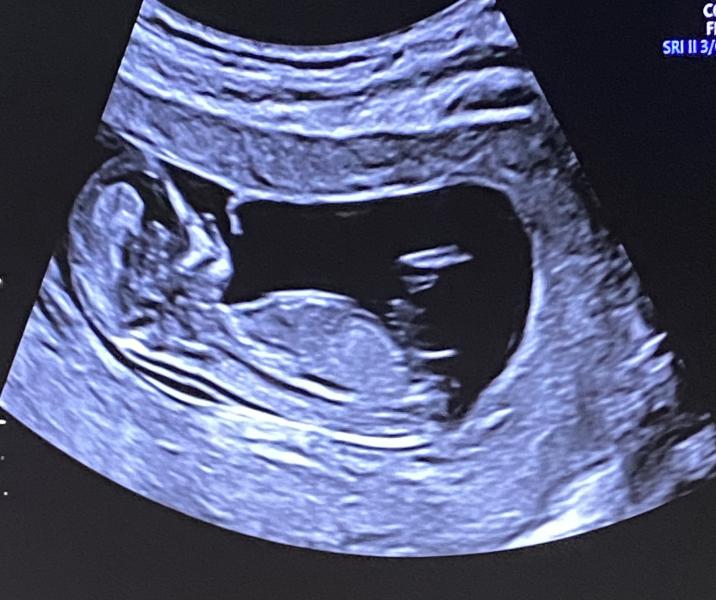

Сходила на первый скрининг. Здесь видно пол ребенка или нет?)

С таким половым бугорком (угол) нам предположили девочку вторую)

Нет, хорошо видно будет чуть-чуть позже, а так только кровь сдавать

Нет конечно. Иной раз узисты по узи не могут на таких ранних сроках сказать, а тут мы обыватели не видя даже писюльку точно сказать не сможем😀. Но я могу вам на 100% сказать что у вас либо мальчик либо девочка 😀

Девочка